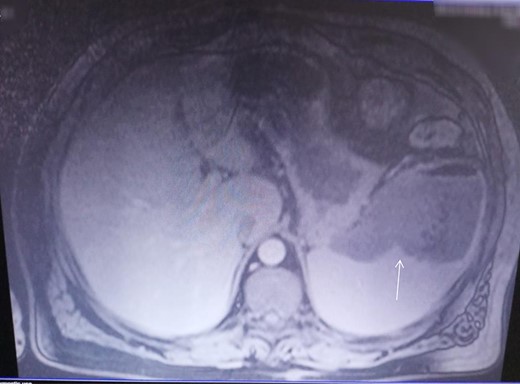

At the admission, erythrocyte sedimentation was 80 mm/h (normal value 3 mm/h), C-reactive protein was 137.7 mg/l (normal value 0.0–6.0 mg/l), leukocytes were 14.2 × 103/μL (normal value 4.0–10.0 × 103/μl), and glycaemia was 14.81 mmol/l (normal value 4.40–6 mmol/l), while other biochemical parameters were normal. The CECT of the abdomen revealed splenomegaly and splenic abscess in the upper pole of the spleen (Fig. 3). No abscesses elsewhere in the body were detected. Systemic hematologic disorders are excluded. Initially, the patient was treated by imipenem- cilastatine. After the admission, on the fourth day, patient underwent open splenectomy. Enterococcus faecalis has been isolated from splenic abscess. On the seventh postoperative day the patient was discharged. The patient was in very good condition a month later after splenectomy. For the lesions on lower legs, based on clinical examination, necrobiosis lipoidica as a diagnosis was confirmed. The disease was in later stage and histopathologic examination was not necessary. This patient was treated by topical administration of steroid cream (Exevate cream 0.05%). After a 2 months follow-up, this treatment was not effective, but continuous to be under surveillance of dermatologists.

CECT investigation revealed abscess and air presence in the upper pole of the spleen.

In a patient with pyrexia of unknown origin, left hypochondriac pain, leukocytosis, and splenomegaly splenic abscess should always be suspected [3]. Our patient presented with a 2-day history of abdominal pain in the left hypochondrium, general malaise, and pyrexia, and with erythrocyte sedimentation, C-reactive protein and leukocytes highly elevated. The CECT imaging of the abdomen revealed splenomegaly and splenic abscess in the upper pole of the spleen.